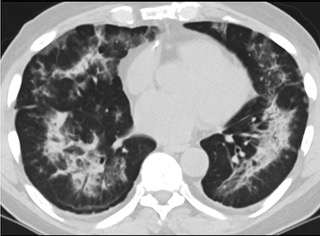

疑点二,中国科研工作者从60篇研究论文中筛选出142位电子烟肺炎患者的250张影像图片,邀请3位放射科权威专家,对上述全部影像图片、相关病人临床信息以及文献原文进行了仔细全面研究与审查,又有了新的发现。

6天后的轴向CT平扫图像显示毛玻璃影变为实变和轻度结构扭曲。(同一病人CT影像)

16位被文献报道为电子烟肺炎的患者被专家判定为“病毒性感染”,即有可能是新冠肺炎的“疑诊患者”,其中更有5位临床症状和治疗情况相对完整的患者被判定为“中度可疑”。因此在2019年美国报道的电子烟肺炎中存在病毒性感染的病例,而且不排除美国电子烟肺炎中存在新冠肺炎的可能性。